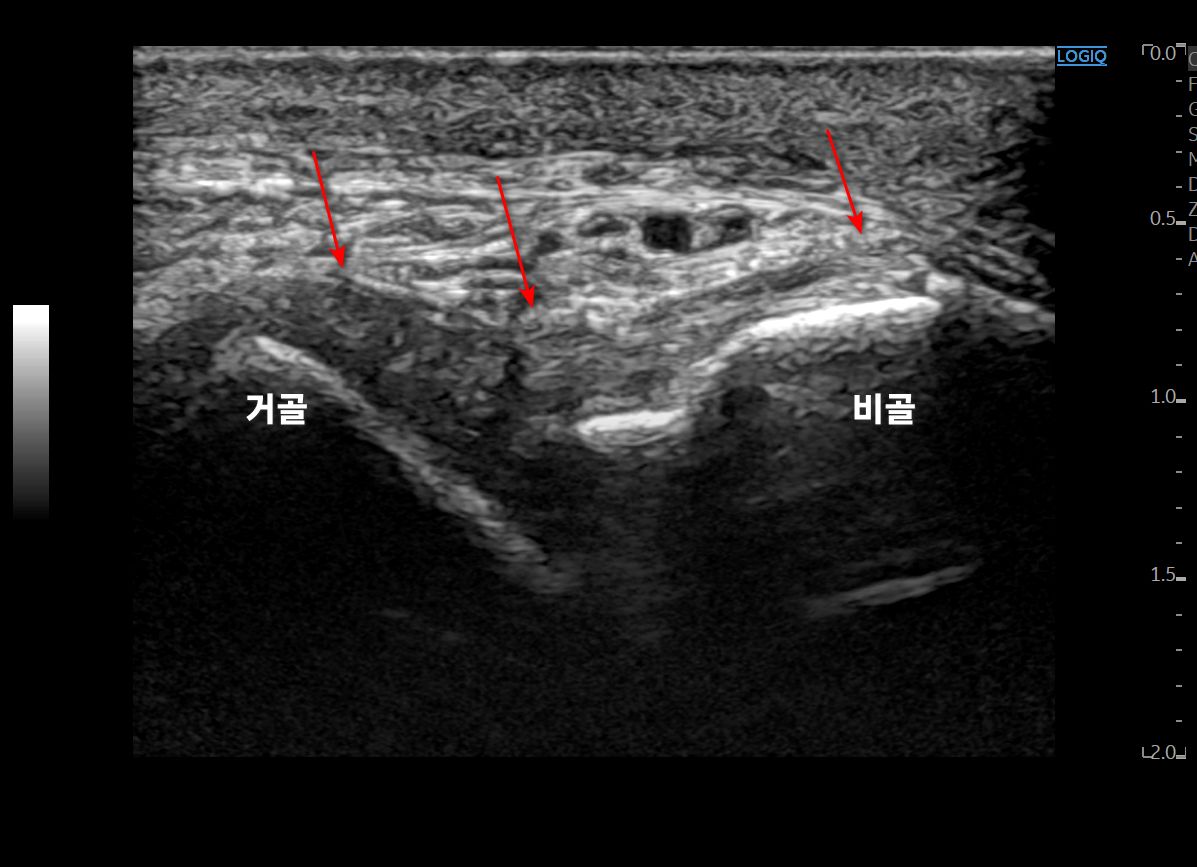

족소양경근에 프로브를 대어

반대쪽과 비교해보았습니다.

왼쪽 영상을 보시면

이분인대가 늘어나면서

종골 전방돌기(anterior process)가

톡 떨어져 나갔네요.

주변 연부 조직도 부어있어

골절이 의심됩니다.